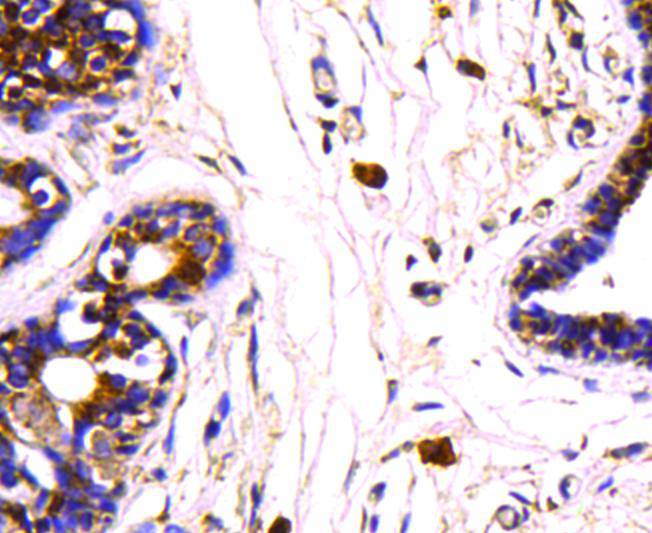

Immunohistochemical analysis of paraffin-embedded mouse testis tissue using anti-HSP70 antibody. Counter stained with hematoxylin.

Immunohistochemical analysis of paraffin-embedded mouse prostate tissue using anti-HSP70 antibody. Counter stained with hematoxylin.